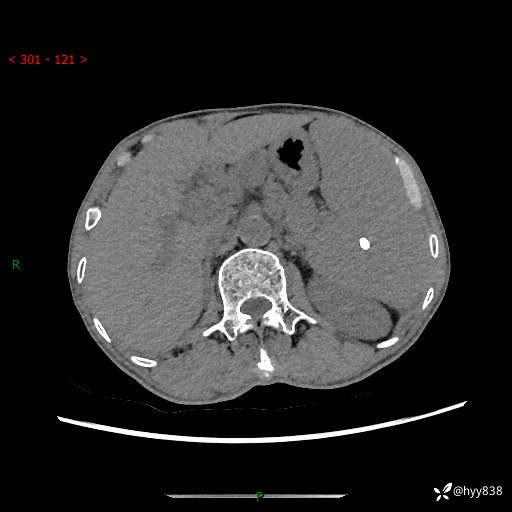

老年男性,脾大并脾脏弥漫粟粒状低密度,淋巴瘤 VS 肉芽肿 VS 血管瘤---结果公布

简要病史: 患者于3月前无明显诱因出现脾大,伴腹部轻微不适,具体不详,无腹痛、腹泻、腹胀,无头晕、头痛、乏力,无恶心、呕吐、呕血,无胸闷、气短、胸痛不适

上腹部CT平扫+增强